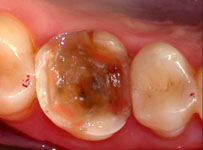

Fig. 2

Vista por vestibular após a redução das cúspides.

O dente 16 apresentava apenas duas cúspides remanescentes e fragilizadas, as quais precisaram ser reduzidas por desgaste (Fig. 1). Após a redução cuspídea, restou uma coroa clínica curta e com assoalho pulpar plano. Devido a essas condições não havia a possibilidade de preparar uma caixa oclusal, os degraus proximais que determinam uma cavidade MOD pois a polpa seria atingida , assim como, estrutura para reter uma coroa total. (Fig. 1, 2 e 3).